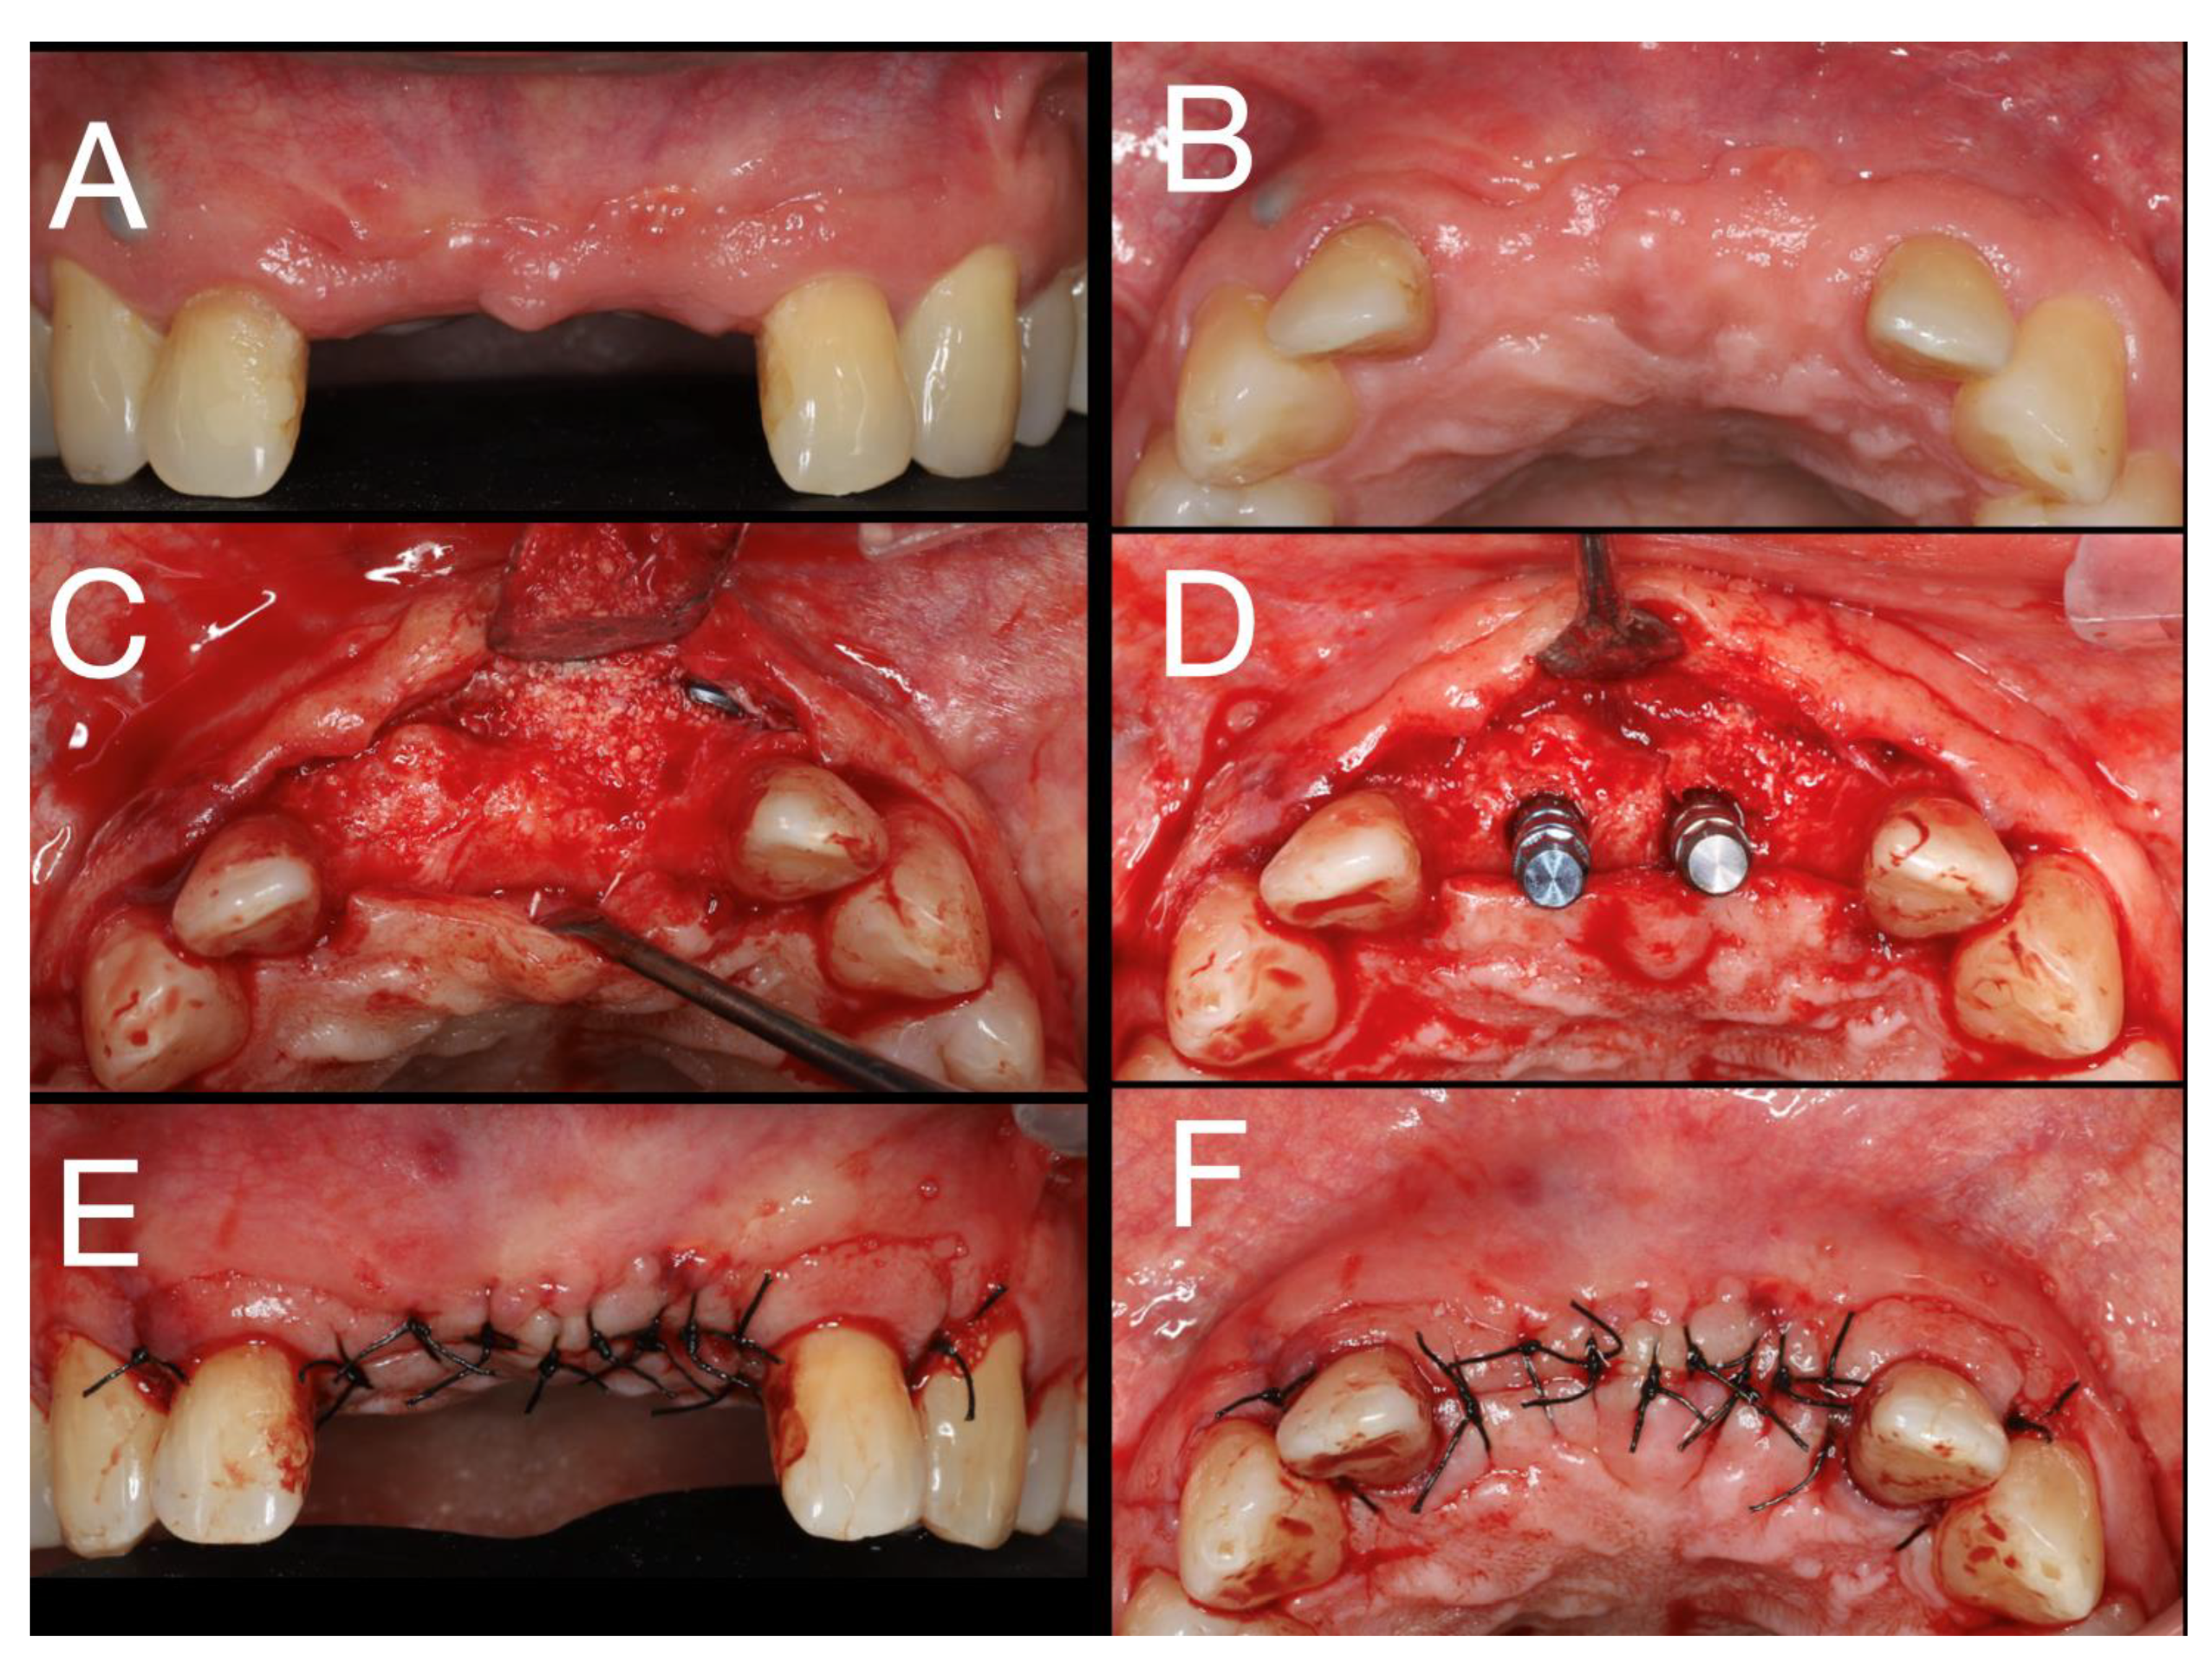

Figure 4. Different view after cyst enucleation.

Local anesthesia with articaine (artinibsa® 40mg/ml + 0.01mg/ml, Inibsa®, Spain) was given. A linear incision with a 15 blade was performed form the distal aspect of tooth 13 to mesial of tooth 23 where a releasing incision that cross the mucogingival line was performed. A full thickness flap was elevated, and the cyst was enucleated (Figure 4). During odontogenic of the cyst enucleation (histological established), special attention was given to maintain the integrity of the anterior nasal spine. Even with the carfule enucleation, a communication with the nasal floor occurred and a loss of the palatine bone plate was observed (Figure 4).

After 6 months, with healing without any adverse event, the placement of the 2 implants was planned (Figure 9A,B).

An incision with a 15 blade between teeth 13 and 23 under local anesthesia with articaine (artinibsa® 40mg/ml + 0.01mg/ml, Inibsa®, Spain) was executed and a full-thickness flap was raised (Figure 9C).

The Bone level® (Straumann®, Swiss) drilling protocol for the two dental implants 4.1x10RC at the region of the teeth 11 and 21 was followed (Figure 9D). The cover screws were placed, and the flap sutured with polyamide 4.0 (Supramida®, B Braun®, Germany)) (Figure 9E,F). As follow-up it, was indicated azithromycin 500mg 1 pill at day for 3 days, ibuprofen 600mg, 12/12h for 4 days, chlorhexidine mouthwash 0,12%, 3 times/day for 10 days and the suture removed after 8 days.

Figure 9. Six months of healing; Surgery of the dental implants placement; A -frontal view; B - occlusal view; C - full-thickness flap - occlusal view; D - Dental implant placement - occlusal view; E -Flap suture frontal view; F -Flap suture - occlusal view.